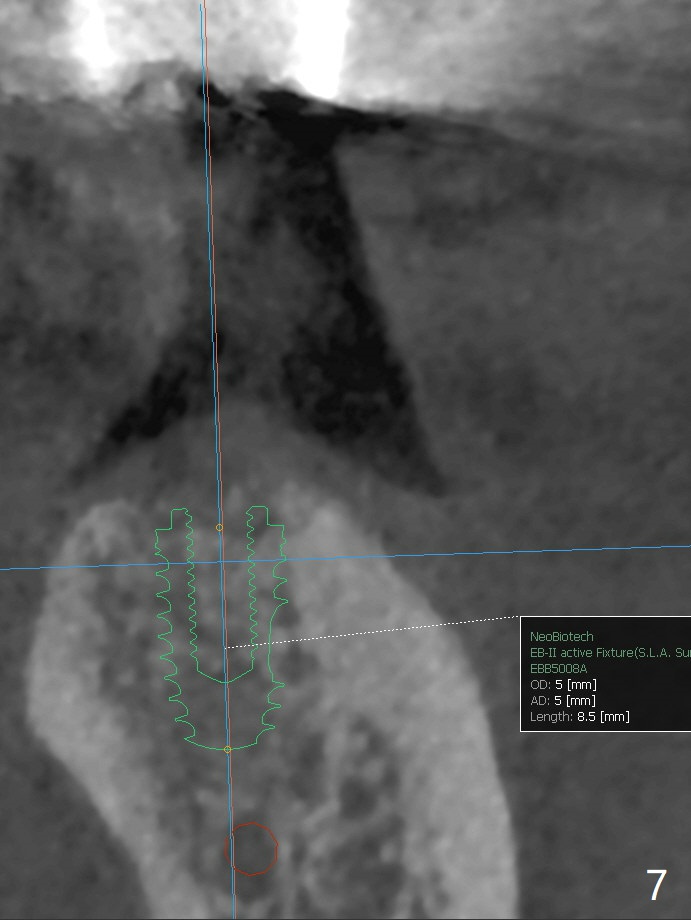

A 49-year-old man returns for #14 and 15 implant impression. The tooth #18 is buccally shifted with mobility, which is incompatible with #14 and 15 restoration. The tooth has to be extracted with socket preservation (Fig.1). A piece of 6-month collagen membrane is used to cover allograft. The socket is healing 9 days postop (Fig.2), probably related to its small wound. Three months and a half postop (Fig.3), CT shows bone healing (Fig.4 sagittal (thin) section, 5 (thick section); 6 (coronal (thin) section). A 5x8.5 mm implant will be placed (Fig.7,8).